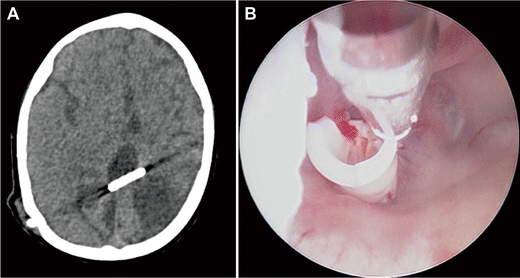

Four-year-old with a complex history of congenital hydrocephalus and multiple ventriculoperitoneal shunt surgeries and revisions. The axial CT scan shows an orphan catheter from a previous surgery (a). The catheter was retrieved endoscopically (b) prior to an endoscopic septostomy and insertion of a new ventricular catheter